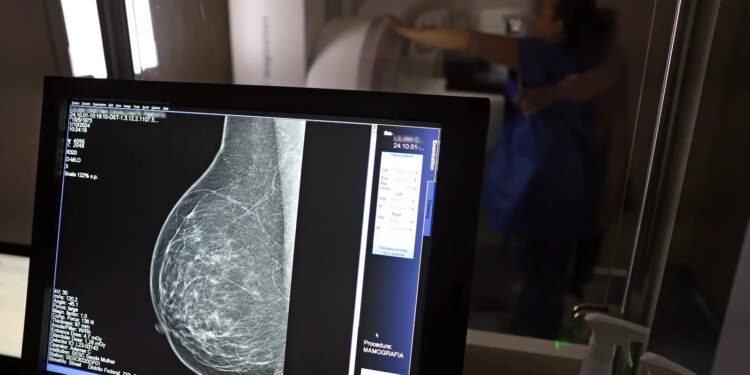

Dados do Painel Oncologia Brasil, analisados pelo Colégio Brasileiro de Radiologia e Diagnóstico por Imagem (CBR), indicam que mais de 108 mil mulheres com menos de 50 anos foram diagnosticadas com câncer de mama no Brasil no período entre 2018 e 2023 – uma média de uma em três mulheres diagnosticadas com a doença.

Para a entidade, os números reforçam a importância de ampliar o rastreamento do câncer de mama por meio da realização de mamografia em mulheres abaixo dos 50 anos e acima dos 70 anos, faixas etárias que não estão incluídas na recomendação padrão de exames preventivos no âmbito do Sistema Único de Saúde (SUS).